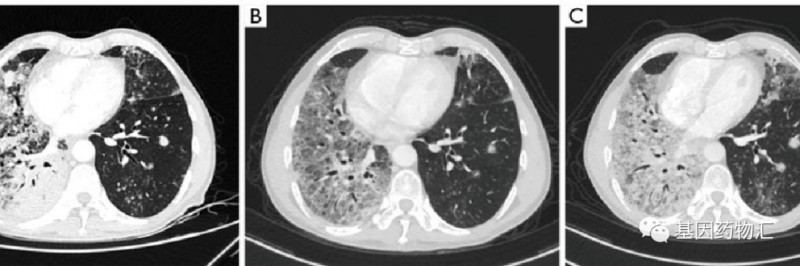

在接受莫博赛替尼治疗的最初5个月里,E先生自我感觉变化很大,呼吸越来越轻松,病灶也缩小了。但在治疗到9个月之后,CT检查发现E先生的双侧肺出现了新的转移病灶,病情再次进展。

果然,E先生再次找到了属于自己的幸运。截至案例发布时,E先生仍然在持续治疗当中,病灶在缩小,无进展生存期超过了9个月,且期间没有出现任何的并发症或不良反应。